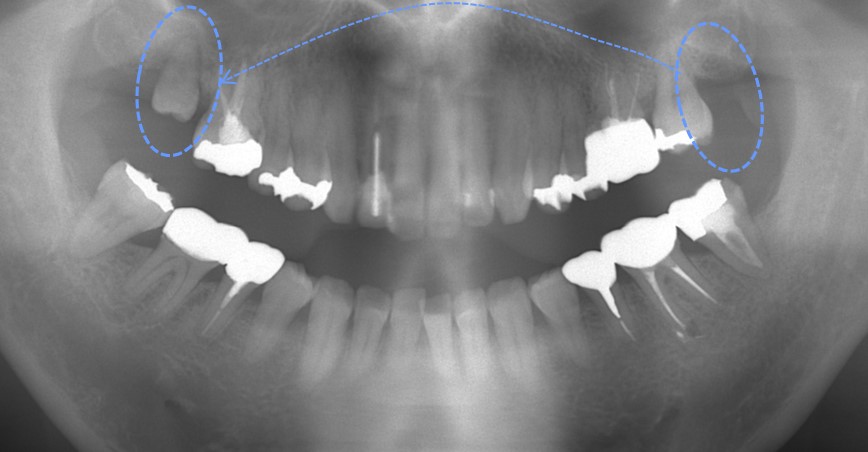

オレンジ〇に囲まれた歯は重度の歯周病になっています。細菌感染によりオレンジ矢印部分の骨が溶けているのがわかります。青〇部分には2つの歯が重なっています。治療計画は、オレンジ〇の歯を抜歯した後に、青○の重なっている歯を移植する計画としました。

オレンジ〇の歯を抜歯した直後です。大きく骨が喪失してしまっています。感染が大きすぎる場合、抜歯した日には移植せず、後日移植します。

抜歯後2週間ほどで青○の歯を移植しました。移植直後の写真です。

移植から4年後の写真です。青矢印部分の骨が大きく再生しています。